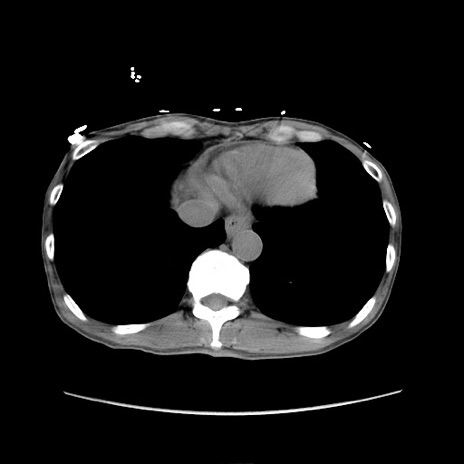

冠状断像

【症例】 60歳代男性

【主訴】 下腹部痛

【現病歴】 本日夜中より下腹部痛の症状認め、受診。

【既往歴】 膀胱癌(膀胱全摘+尿管皮膚瘻術) 、胃癌術後

【身体所見】 BT 35.3℃、PR 58/min、BP 136/98mHg、腹部平坦、軟、腸蠕動音±、ストマ留置あり、左上腹部~正中部に圧痛あり、反跳痛なし。

【データ】WBC 5100、CRP0.01